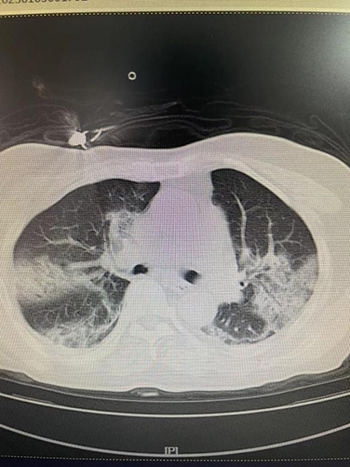

▲患者患新冠重症肺炎

重症病房饱和,一时难以转入,骨科医生们遇到了棘手的新问题。新冠不愈,随着时间的推移,骨折可能在畸形的位置上悄悄生长,手术难度更大,对患者的身体条件要求越高,甚至手术成为一种奢望。此时,罗令教授给大家鼓劲:“尽管我们不是专科医生,别忘了,我们有强大的医院做后盾,我们可以学习,一定要帮助患者克服困难,早日手术。”郭强主治医师正经历着新冠的发烧,汤逸夫、彭平博士刚做完一夜的断指再植手术,依然会坚持早晚查房,会同黄煜钊博士,24小时轮流守候在病房,与护士老师们一道监护着包括老李在内的新冠病人,及时处理病情的变化,随时协调内科的会诊救治。责任、信心,加上呼吸、重症、麻醉等相关科室老师们及时有效的治疗指导,一周后“有心人终不负”,患者的整体情况迎来转机,血氧饱和度依靠吸氧能够维持在90%以上,症状较前明显减轻,肺部CT也显示较前好转。